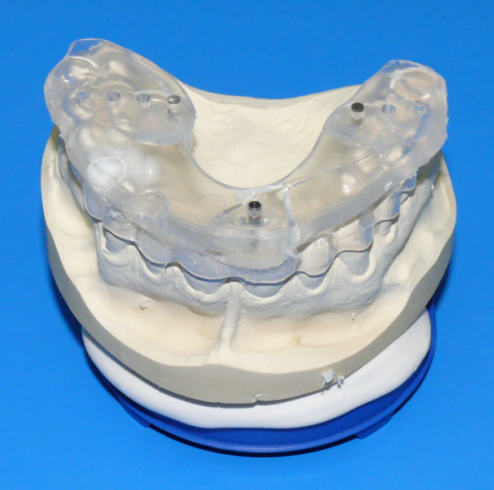

Following a wax-up and set-up of the planned prosthetic restoration, a scan template was created for every patient in accordance with the principle of backwards planning, which starts with study casts. Three titanium pins were inserted into the scan templates lingual to the tooth row for the spatial referencing of image data and image fusion (Figure 5 [Fig. 5]).

Figure 5: Scan template after the preparation of a wax-up and set-up of the planned prosthetic restoration. Three titanium pins were attached lingual to the tooth row by polymerization.